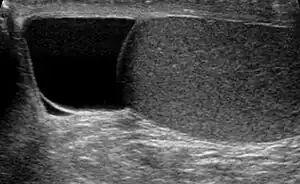

| Ultrasound of a testicle (grey) and a spermatocele (black). | |

The primary care physician may diagnose and manage benign causes of scrotal masses such as hydrocele, varicocele and spermatocele. However, if a "must not miss" diagnoses related to testicular masses such as testicular torsion, epididymitis, acute orchitis, strangulated hernia and testicular cancer is suspected, the family physician must refer to a urologist.[16] Finding a painless, cystic mass at the head of the epididymis that is clearly separate from the testicle can indicate a spermatocele. Shining a light through the mass through a process known as transillumination can also help differentiate between a fluid-filled cyst and a tumor, which would not allow as much light to pass.[17] If uncertainty exists, ultrasonography of the scrotum can confirm the presence of a spermatocele.[14] The location and history of any scrotal masses are crucial in determining whether or not the mass is benign or malignant.[18] Lab tests such as a complete blood count (CBC test) or urine test can also be conducted to check for any possible infection or signs of inflammation.[19]

Spermatoceles come in varying sizes and shapes. Some spermatoceles are very small and can only be detected through an ultrasound. More commonly seen are spermatoceles that are a pea-sized lump. They tend to form above or behind a testicle and have a shape and size that looks like a pea. Larger growths have been reported to look similar to a third testicle and can be very discomforting.[19] For those who are affected with large spermatoceles, some have reported feeling pain, heaviness, and fullness in the affected testicle.[17]